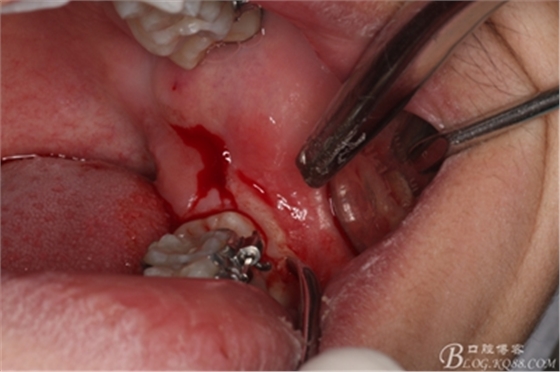

圖5.行遠(yuǎn)中水平切口+37近中垂直切口

圖6.兩個切口的交界處翻瓣